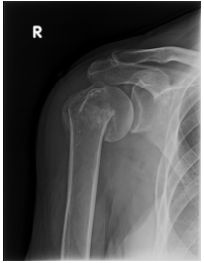

57 一位 60 歲女性主訴 2 天前在浴室滑倒,右肩疼痛求診,X 光顯示如下圖。下列敘述何者最不適當? (A)可預估患者跌倒時上臂在內收位,軀幹向傷側傾斜,手掌或肘部著地 (B)手法復位後,須用上臂超肩關節夾板固定 (C)睡覺時要仰臥,並在肘後部放一枕頭以維持肩部於前屈位,且維持肩關節在內收位,以利骨折之復位 (D)此種骨折也有可能傷及神經,最常見者為腋神經